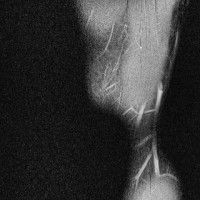

무릎 mri 간단히 봐주실 수 있으시나요 ㅠㅠ

안녕하세요 8년전 십자인대 수술하고 최근 무리한 운동에 무릎 불편감이 생겨서

mri 찍었습니다.

진단결과는 첫 찍은 병원에서 활액막염 이라는 진단을 받았습니다. 혹시 봐주실 수 있으실까요?

올라온 MRI가 단편적이라서 정확한 진단에 어려움이 있지만 십자인대에는 큰 이상이 있지는 않은것 같으며, 무릎관절내 물이 있는 것으로 보아 활액막염의 진단이 맞을 것 같습니다.

하지만 단편적인 영상이기 때문에 촬영병원에서 정확한 판독지 등을 받으시는 것이 좋겠습니다.